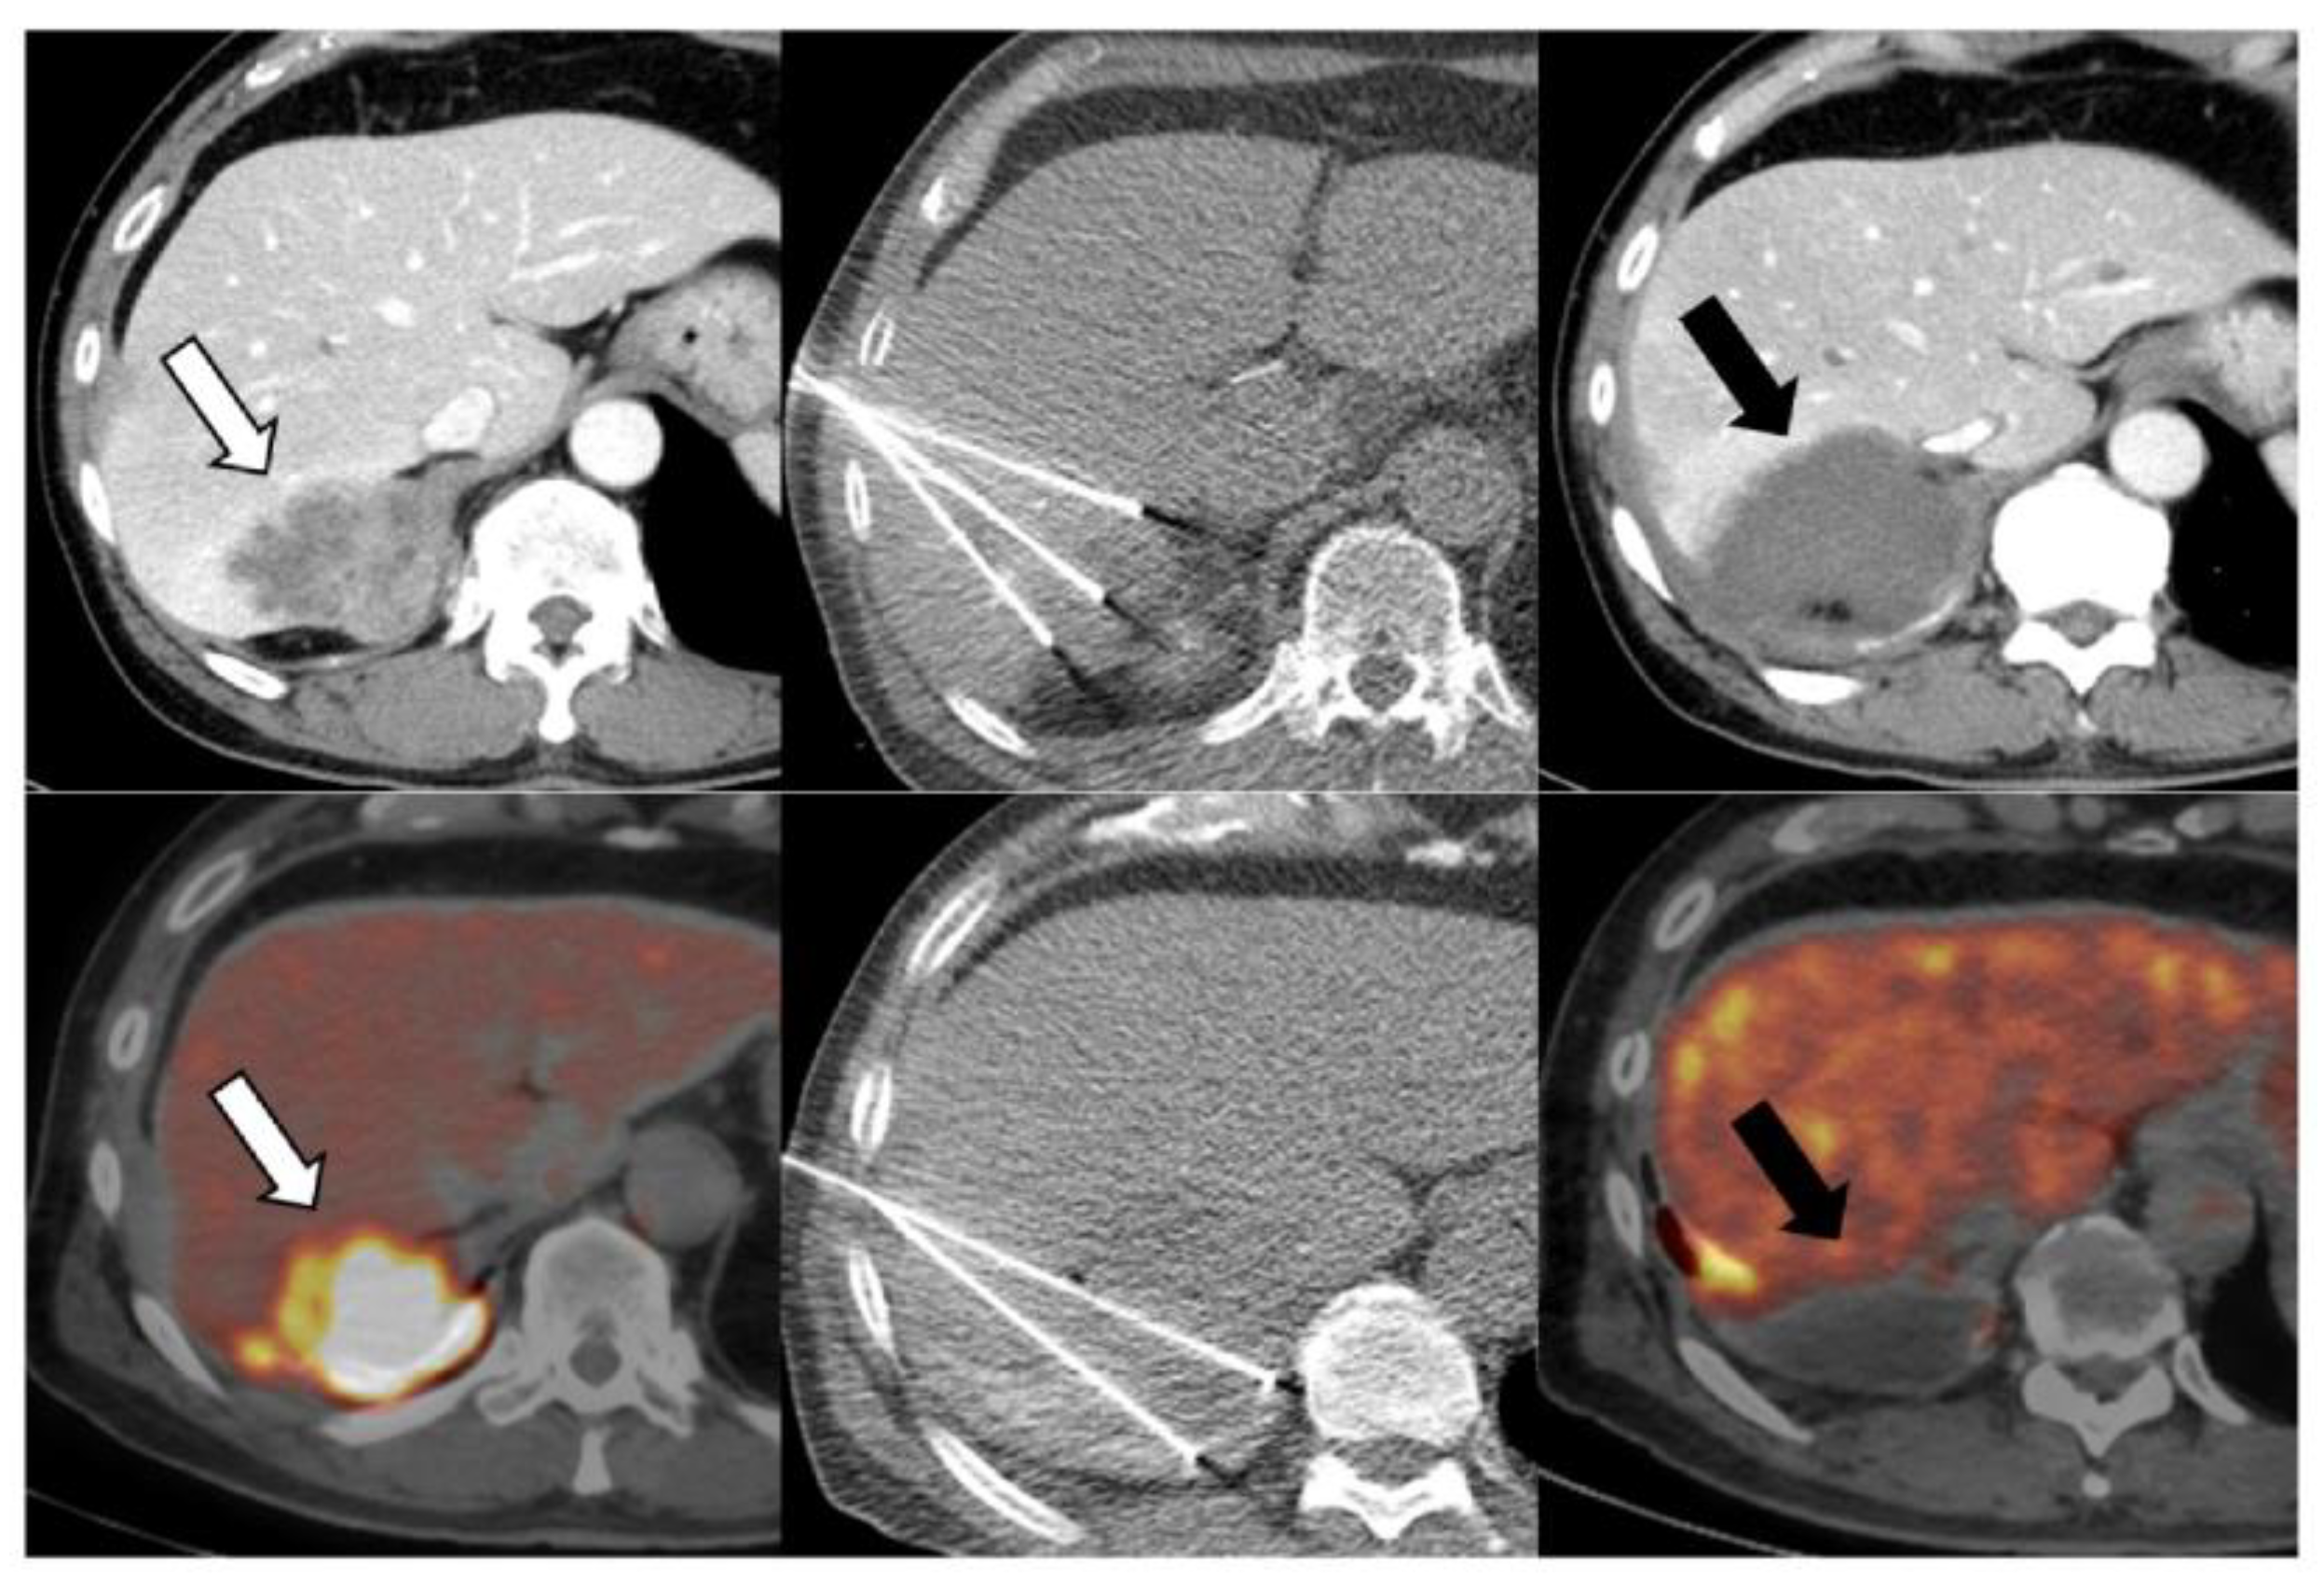

Background/Objectives: Pleural mesothelioma (PM) frequently recurs despite multimodal therapy. Here, we aimed to retrospectively evaluate the safety and potential clinical benefit of radiofrequency ablation (RFA) for recurrent PM. Methods: Fourteen consecutive patients underwent CT-guided RFA between July 2019 and June 2025. The cohort comprised 13 men and 1 woman, with a median age of 69 (range, 54–77) years. All patients had previously received systemic therapy and 12 had undergone surgery. Seven patients (50%) presented with multiple lesions, and 25 tumors (median diameter 1.8 cm; range, 0.5–7.0 cm) were treated in 23 sessions. Outcomes assessed were local tumor control, complications, and survival. Local progression and overall survival were estimated using Kaplan–Meier analysis. Adverse events were classified according to the Society of Interventional Radiology guidelines. Results: Technical success was achieved in all sessions. Two tumors showed local recurrence, corresponding to 1- and 2-year local progression rates of 10.6%. Seven patients showed distant metastases, most of whom subsequently received systemic therapy. Three patients died, two from disease progression and one from treatment-related gastrointestinal perforation during therapy for an unrelated cancer. The overall survival rates were 100%, 100%, and 60% at 1, 3, and 5 years, respectively. Major and minor complications occurred in one case each (4.3%): a refractory skin ulcer and retroperitoneal hematoma, respectively. Conclusions: RFA was technically feasible and generally well tolerated, and helped achieve encouraging local control and survival in patients with recurrent PM, warranting further evaluation of RFA as a complementary approach in multimodal treatment strategies.